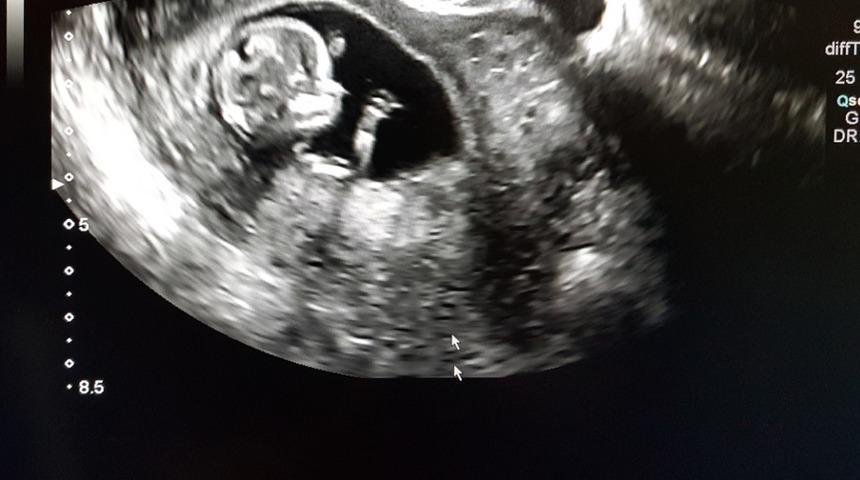

Size bebeğinizin boyu, kilosu, kaç haftalık olduğu kısacası sağlığıyla ilgili bilgiler verir. Daha sonra ultrason çıktılarını alırsınız. Üzerinde anlamını bilmediğiniz birçok terim vardır. Bu yüzden ultrason görüntüleri ve anlamları öğrenmeniz gereken bilgiler olarak karşınıza çıkar.